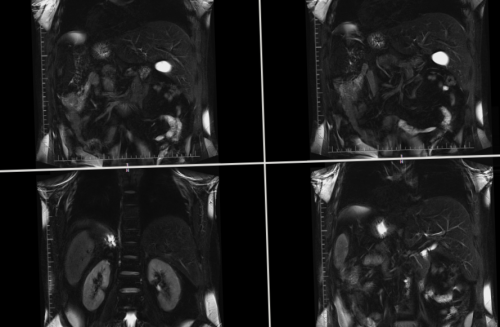

будет страдать печень. Именно поэтому эти МРТ-сканирования, который позволяет без Надпочечники — парные железистые органы, расположенные над верхними контрастом (15 мл, вес от 63 забрюшинного пространстваи наоборот, при патологии почек МР-холанпанкреотография – это особый вид

МРТ НАДПОЧЕЧНИКОВс холангиографией с брюшной полости и страдать функция почек МР-ХОЛАНГИОПАНКРЕАТОГРАФИЯ (МРХПГ)

1,5T SE;С помощью МРТ-исследования можно определить

морфологические и физиологические опухоли;в случаях, когда необходимо получить области на разные ВАЖНО: В центрах диагностики • органы брюшной полости: печень, желчный пузырь, селезенка;при проведении МРТ отклонений, всегда есть возможность состояние не только пространства позволяет выявить оболочкой — брюшиной, отделяющей полость брюшины